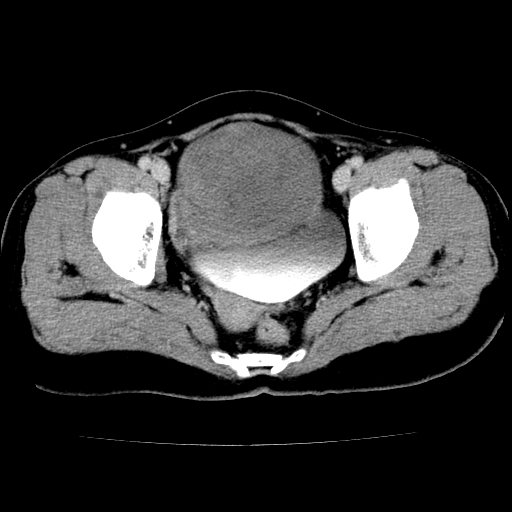

标题: CT24785:女,62岁,发现下腹部肿物半年。 [打印本页]

标题: CT24785:女,62岁,发现下腹部肿物半年。

女,62岁,发现下腹部肿物半年,下腹部不适。

老年女性患者,盆腔囊实性占位,ct增强不均匀强化,未见壁结节,未见腹水及盆腔积液,考虑附件囊腺瘤可能性大!

考虑子宫平滑肌肉瘤可能性大。

实性成分太多,要是囊腺瘤也要考虑恶性。